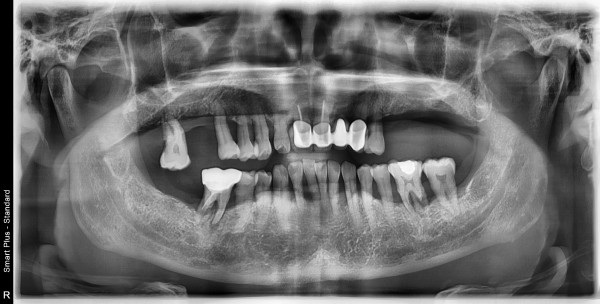

56세 이**님의 치료전

치료시작일 2020.10.13

촬영장소 온가주치과의원